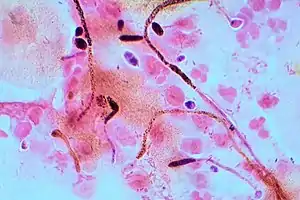

Gram stain (Gram staining or Gram's method), is a method of staining used to classify bacterial species into two large groups: gram-positive bacteria and gram-negative bacteria. It may also be used to diagnose a fungal infection.[1] The name comes from the Danish bacteriologist Hans Christian Gram, who developed the technique in 1884.[2]

Gram staining is a bacteriological laboratory technique[6] used to differentiate bacterial species into two large groups (gram-positive and gram-negative) based on the physical properties of their cell walls.[7] Gram staining can also be used to diagnose a fungal infection.[1] Gram staining is not used to classify archaea, since these microorganisms yield widely varying responses that do not follow their phylogenetic groups.[8]

Gram-indeterminate bacteria do not respond predictably to Gram staining and, therefore, cannot be determined as either gram-positive or gram-negative. Examples include many species of Mycobacterium, including Mycobacterium bovis, Mycobacterium leprae and Mycobacterium tuberculosis, the latter two of which are the causative agents of leprosy and tuberculosis, respectively.[26][27] Bacteria of the genus Mycoplasma lack a cell wall around their cell membranes,[9] which means they do not stain by Gram's method and are resistant to the antibiotics that target cell wall synthesis.[28][29]